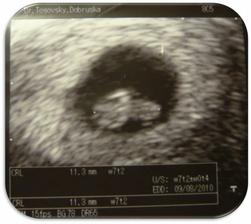

Tak jsme se konečně dočkali a den před Štědrým dnem (23.12.2009) jsme se oficiálně z UTZ dozvěděli, če čekáme miminko 🙂 TP 11.8.2010, původní váha 50kg, tak uvidíme, kam se až dostaneme 🙂)

4.2.2010 UTZ - 13tt+4, měříme 76mm, NT screening ... v pořádku